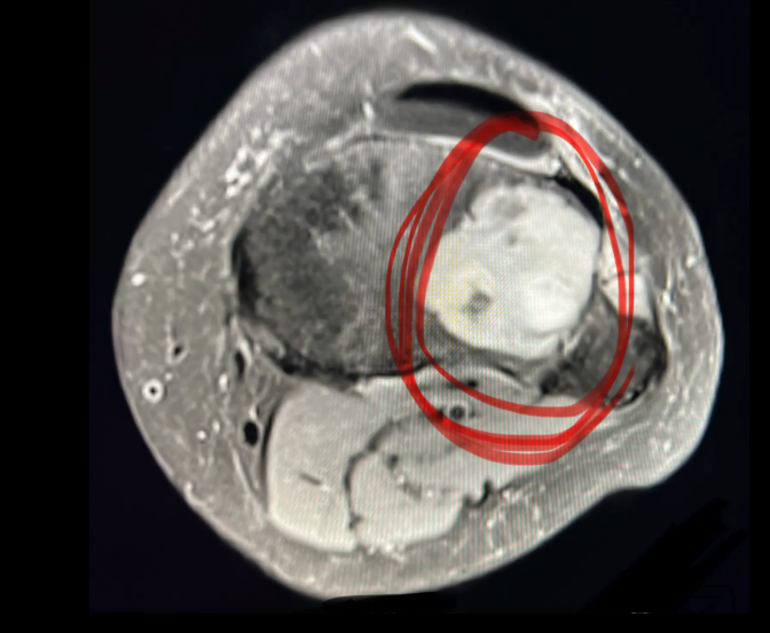

Havaalanında tekerlekli sandalye kullanarak Los Angeles'a geri döndü ve nihayet aralık ayının ortalarına doğru MR'ını çektirdi. Sonuçlar ürkütücüydü: Bacağının içinde devasa bir tümörün büyüdüğü gün gibi ortadaydı ancak MR görüntüsünde onu görmesine rağmen, bunu kendisine açıklayacak birini bulmak ve sağlığı için atması gereken sonraki adımları öğrenmek için savaşmak yine savaşmak zorunda kaldı.

İşte o zaman herkes nihayet onu ciddiye almaya başladı. Ashley'nin The Post'a anlattığına göre, MR sonuçlarına bakan doktor ona “çok büyük” bir dev hücreli bir tümöre sahip olduğuna düşündüğünü söyledi.

Ashley “Bacağımı kaybetmek istemiyordum çünkü tümör kemiğimi yiyordu. Bunu hissedebiliyordum. Kaval kemiğimi tehlikeye atıyordu ve büyümeye devam edecekti.” dedi.

Aylar sonra nihayet kendisine agresif ve milyonda bir görülen bir tümörü olduğu ve derhal alınması gerektiği, aksi takdirde içinde büyümeye devam edeceği söylendi.

Ortopedi ve Travmatoloji Uzmanı Dr. Tarık Elma, kemiklerde görülen dev hücreli tümörlerin aslında kötü huylu kanserlerden olmadığını fakat iyi huylu tümörler olmasına rağmen bulunduğu kemikte aynen bir elma kurdunun elmayı içten kemirmesi gibi bulunduğu kemiği içten çürütmeye ve inceletmeye başladığını söyledi.